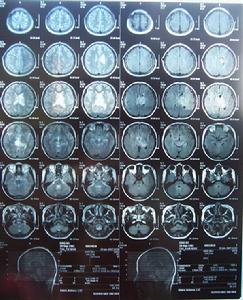

三腦室腫瘤MRI2.腰椎穿刺及腦脊液檢查:病人顱內壓力增高,腦脊液的蛋白含量及鈉含量增高。

5.腦CT檢查:可顯示腫瘤所在的部位、側腦室大小及形狀,對腦室內腫瘤的診斷提供依據。

6.MRI檢查:可顯示腫瘤所在的部位、大小及形狀,來源於腦室內或腦室外、與周圍腦組織關係等,提供可靠的依據。